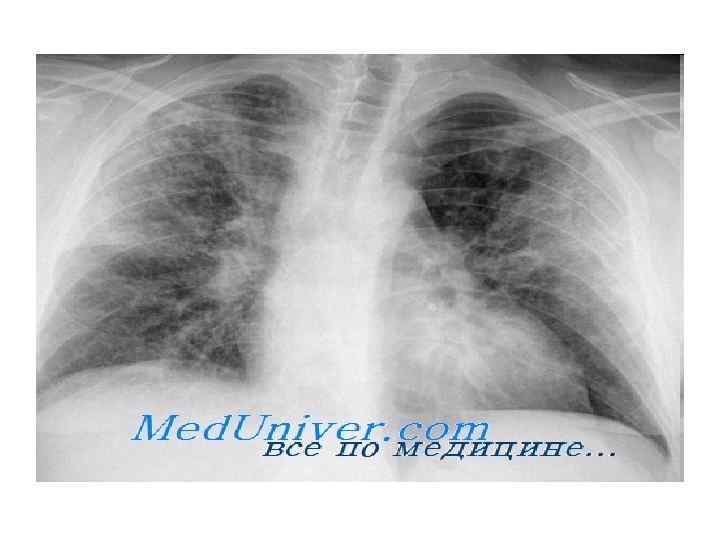

Левое предсердие на рентгенограмме. Левый желудочек на рентгенограмме Различают несколько классических признаков увеличения левого предсердия. Первый признак — расширение ушка левого предсердия, которое определяется на прямом снимке как локальное выбухание в месте, где обычно присутствует впадина между левым стволом ЛА и левым краем ЛЖ. Второй признак — ЛП, увеличиваясь, в силу своего положения смещает вверх ствол главного левого бронха.

По мере этого увеличивается килевидный угол. Третий признак — увеличение левого предсердия кзади, что приводит к локальному отклонению нижней части грудной аорты влево. Это отклонение следует отличать от искривления при прогрессирующем атеросклерозе, при котором поражается нисходящая аорта или в верхнем отделе, или диффузно. Четвертый признак — при заметном увеличении ЛП в прямой проекции может быть виден двойной контур, т. к. ЛП выбухает как вправо, так и кзади и отделяет контур наполненного кровью ЛП от окружающей воздушной ткани легкого. Наконец, на боковом снимке увеличенное левое предсердие видно как выбухание, направленное кзади.

Изолированное увеличение левого предсердия у взрослых развивается вследствие стеноза МК, а заметное увеличение ЛП является характерным признаком порока МК. При митральном стенозе (МС) заметно изменение сосудистого рисунка легких (часто с линиями Kerley В), и в результате прогрессировапия заболевания происходит обязательное увеличение ПЖ. ЛЖ сохраняет нормальные размеры.

При митральной регургитации постепенно увеличивается объем как левого предсердия, так и левого желудочка. Изменение сосудистого рисунка легких более характерно для MP, чем для МС, из-за дилатации ПЖ. Также важно отметить обызвествление кольца МК. Эта частая находка не имеет четкой связи с дисфункцией клапанов, по всегда сочетается с ранней ишемической болезнью сердца.

Левый желудочек на рентгенограмме Для увеличения левого желудочка характерна выступающая, расширенная и направленная вниз верхушка, что следует отличать от поперечною смещения при увеличении ПЖ. На рентгенограмме в ЗП проекции поперечный контур сердца также, как правило, увеличивается, хотя это песпецифичный признак. На боковом снимке увеличение ЛЖ видно как выбухание, расположенное кзади и ниже уровня кольца МК. Оно также может быть ниже и смещать газовый пузырь желулка.

Такое увеличение левого желудочка, расположенного как бы за границами трудной клетки, служит еще одним доказательством необходимости полной и тщательной интерпретации рентгенограммы грудной клетки.

Изолированное увеличение левого желудочка у взрослых бывает при недостаточности АК, часто с дилатацией корня аорты, a MP приводит еще и к дилатации ЛП. И наоборот, стеноз аортального клапана характеризуется в большей степени гипертрофией ЛЖ, чем его дилатацией, которая развивается только в сочетании аортального стеноза с сердечной недостаточностью.

У большинства пациентов с ОИМ тень сердца не увеличивается, но возникает усиление легочного рисунка, связанное с резким повышением конечного диастолического давления левого желудочка. Это состояние проще диагностировать, если сравнивать с предыдущими и повторными рентгенограммами грудной клетки. После ИМ могут появиться различные изменения. Аневризмы ЛЖ, как истинные (в основном в бассейне левой передней нисходящей коронарной артерии), так и ложные (обычно затрагивают основание или заднюю стенку), возникают нечасто.

И хотя они локализуются в разных местах, рентгенологически выглядят одинаково — локальное выпячивание (переднебокового контура сердца при истинной аневризме), где могут быть линейные обызвествления миокарда, края необычно отчетливы, поскольку в области аневризмы нет нормальной сердечной пульсации. Лучше всего аневризмы определяются при сравнении последней рентгенограммы с предыдущими рентгенограммами грудной клетки.